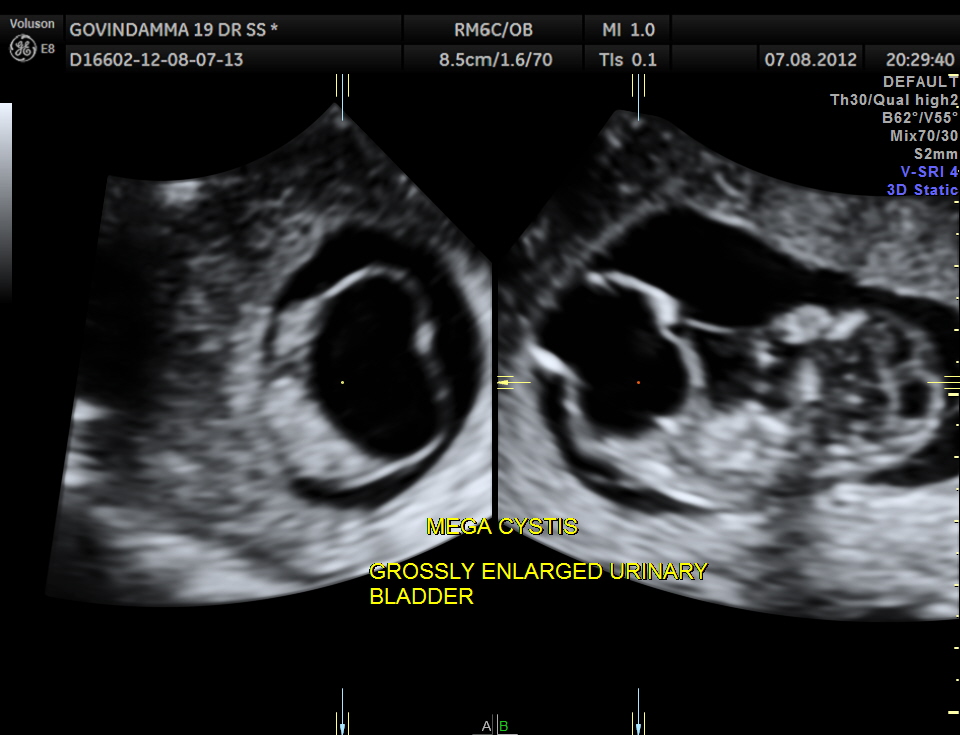

This was a 19 year old primi with history of consanguinity.The scan was done in the first trimester.

A large cystic mass was made out in the lower abdomen.

Will show an enlarged bladder